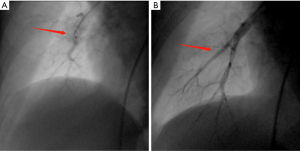

All BPA procedures in the present study were successfully performed without any deaths or major complications. Analysis showed that the vessel was dilated successfully by angiography after BPA (Figure 1). RHC data before vs. after BPA are presented in Table 2. Notably, some RHC hemodynamic parameters including PASP (60.97±21.13 vs. 54.43±18.65 mmHg, P<0.001), pulmonary artery diastolic pressure (PADP) (20.17±6.91 vs. 17.20±6.50 mmHg, P=0.006), mPAP (35.17±10.79 vs. 32.10±10.02 mmHg, P=0.009) and PVR (7.34±4.19 vs. 6.41±3.96 Wood units, P=0.014) were significantly improved after BPA (Figure 2). However, mean PCWP, CI and mean RAP did not show significant changes after BPA.